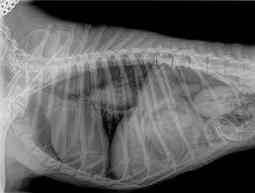

Rayos X

Esta equipo básico nos permite detectar masas y anormalidades dentro de nuestros pacientes antes de recurrir a la cirugía exploratoria.